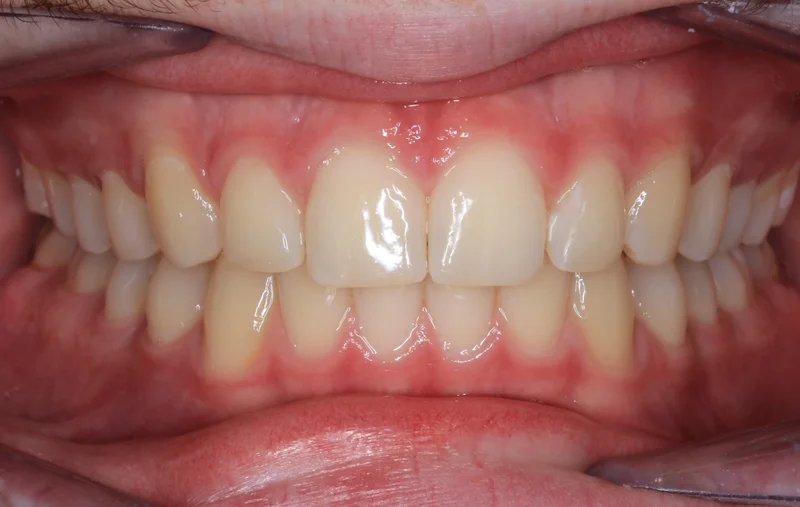

Center Bite

Center Bite - After Treatment

After